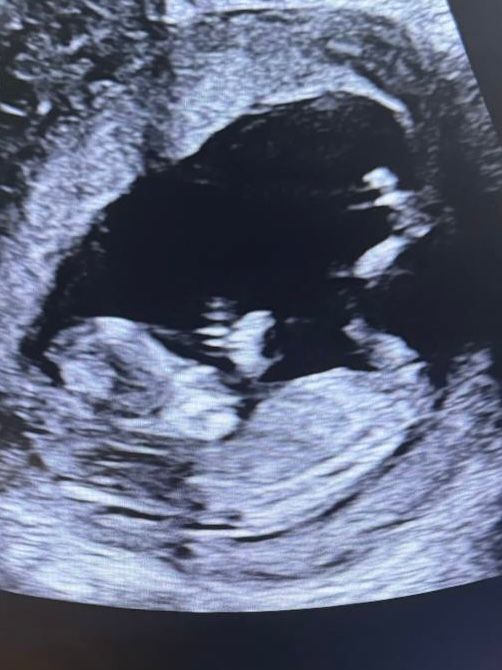

УЗИ пол ребёнка

Скорее всего это девочка

Девочка скорее всего, бугорок параллелен ногам